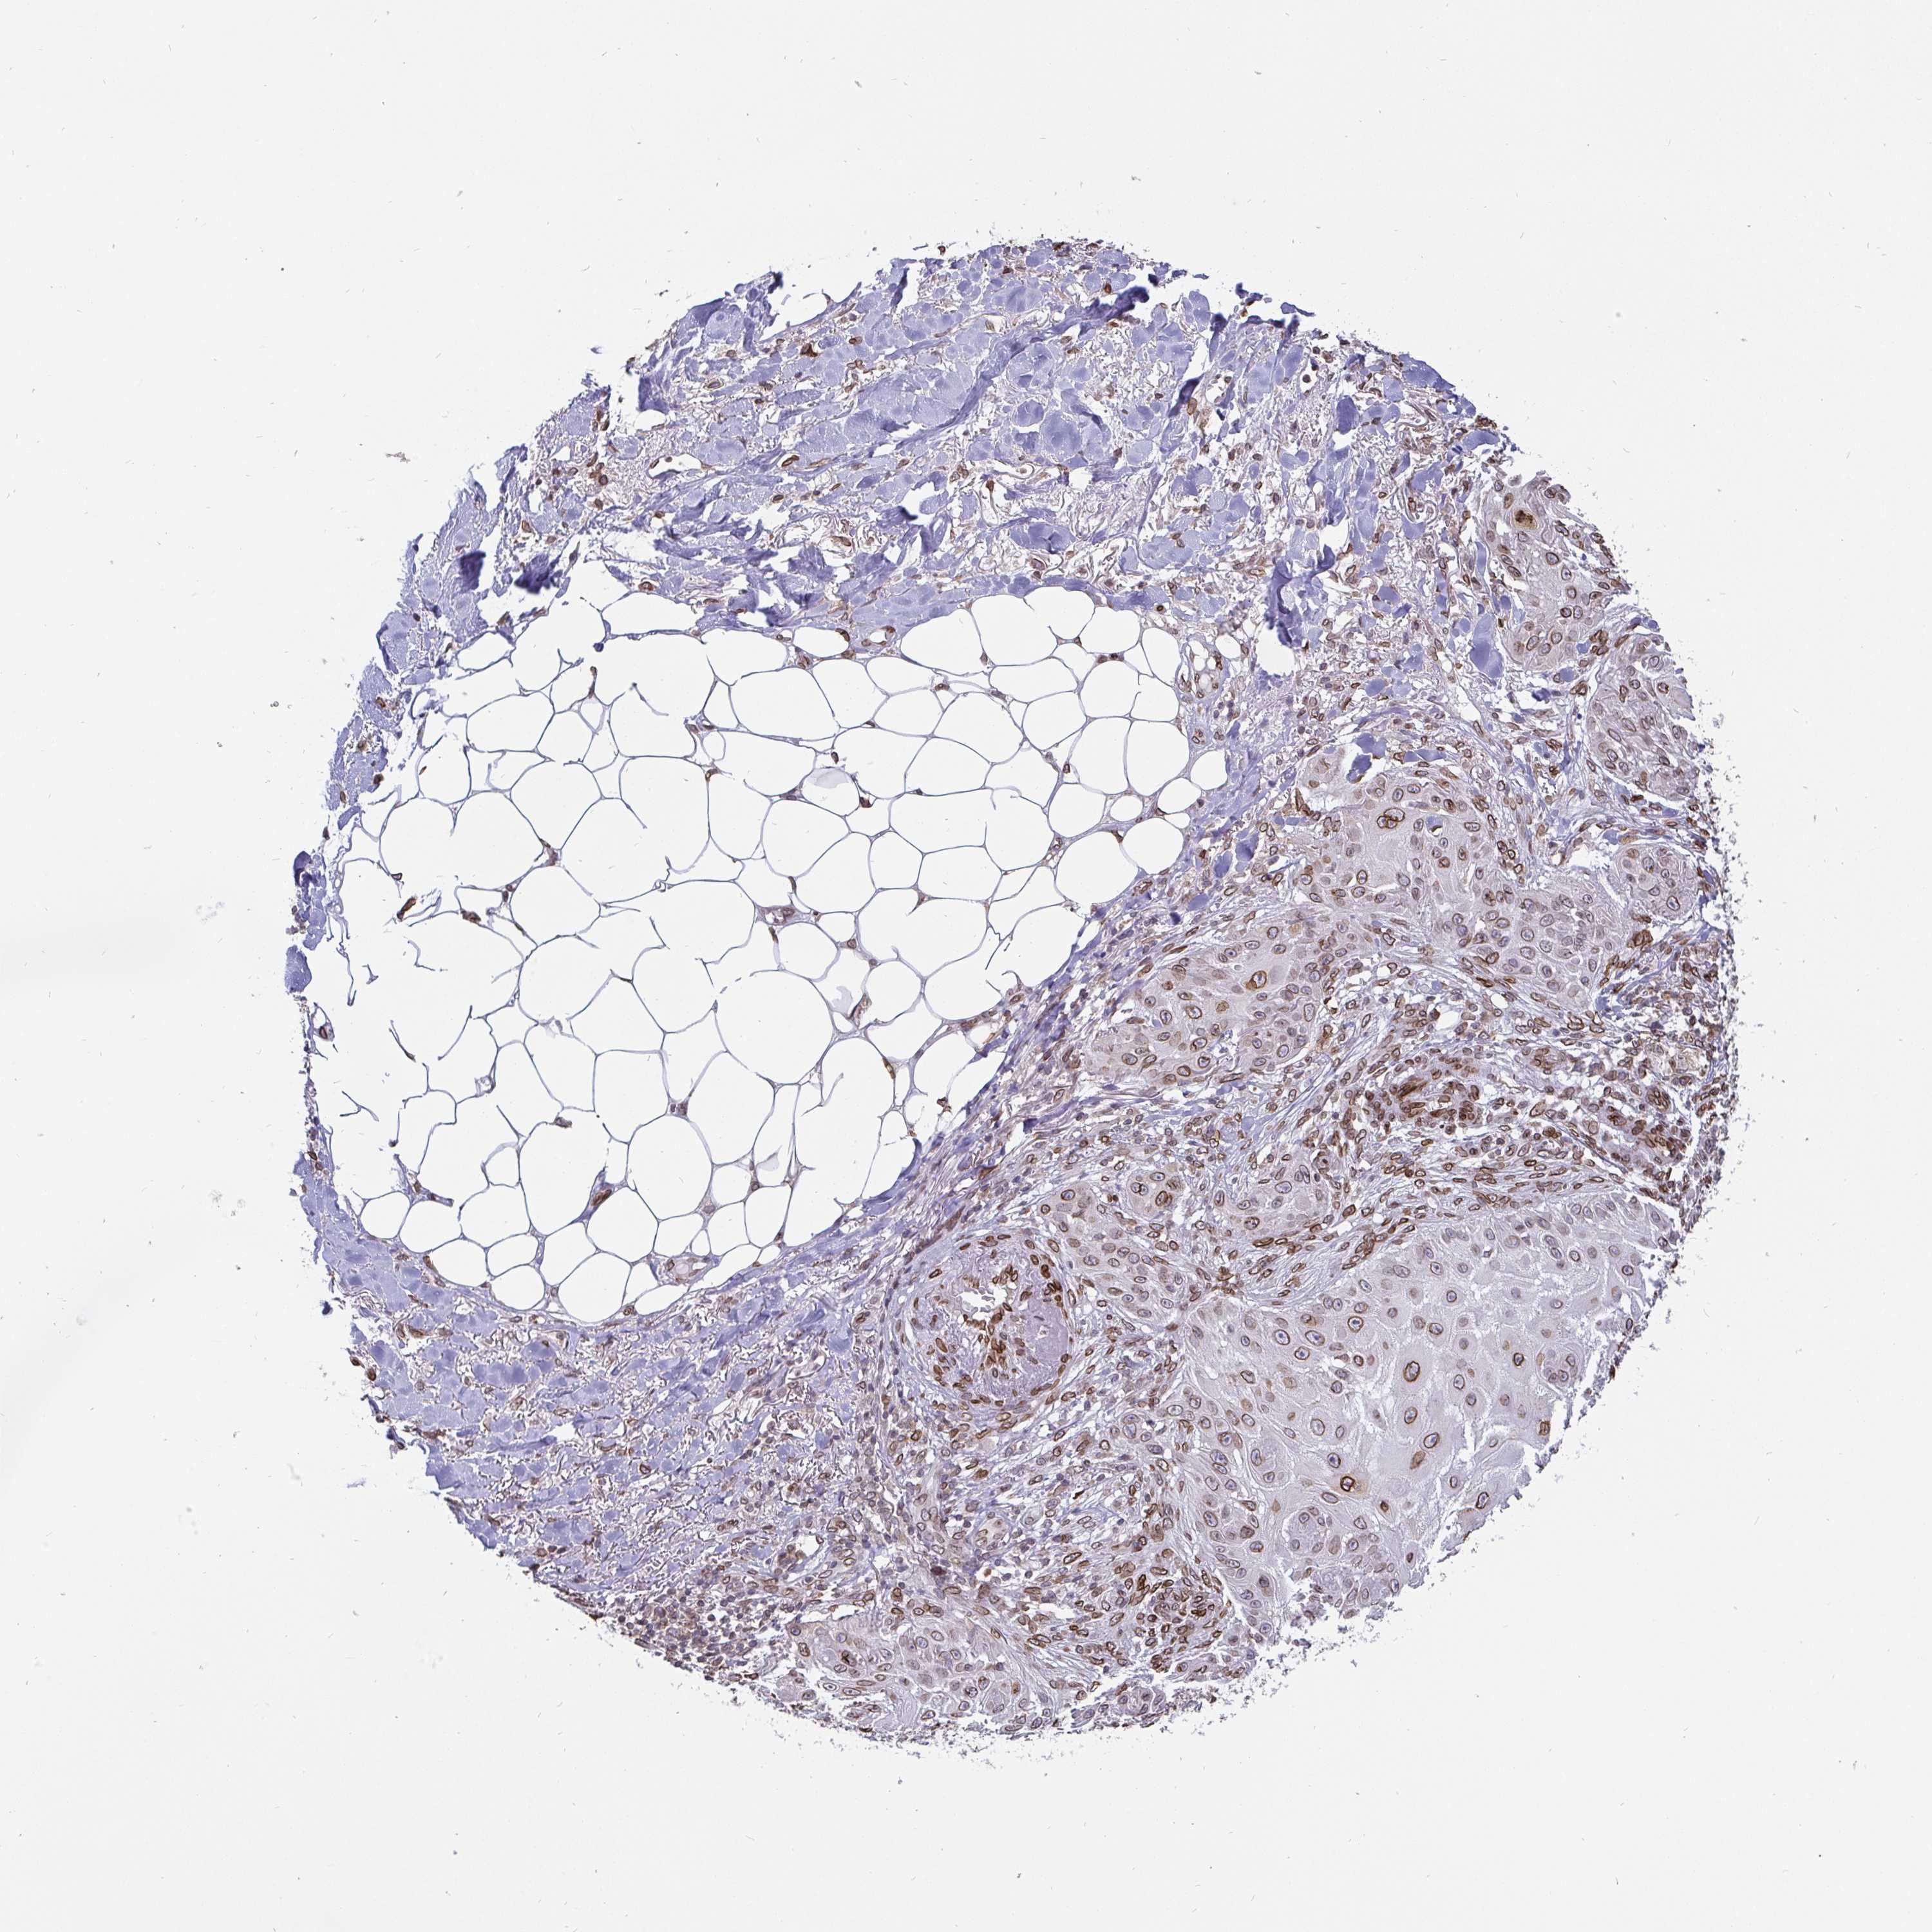

SKIN CANCER - Protein expressioni

A mouse-over function shows sample information and annotation data. Click on an image to view it in a full screen mode. Samples can be filtered based on level of antibody staining by selecting one or several of the following categories: high, medium, low and not detected. The assay and annotation is described here.

Antibody stainingi

Antibody staining in the annotated cell types in the current human tissue is reported as not detected, low, medium, or high, based on conventional immunohistochemistry profiling in selected tissues. This score is based on the combination of the staining intensity and fraction of stained cells.

Each image is clickable and will lead to virtual microscopy that enables deeper exploration of all samples and also displays staining intensity scores, fraction scores and subcellular localization as well as patient and tissue information for each sample.

Antibody HPA000609

Antibody CAB001545

Antibody CAB002029

Antibody CAB062552

Staining

High

Medium

Low

Not detected

Intensity

Strong

Moderate

Weak

Negative

Quantity

>75%

75%-25%

<25%

None

Location

Nuclear

Cytoplasmic/membranous

Cytoplasmic/membranous,nuclear

Basal cell carcinoma

Squamous cell carcinoma, NOS